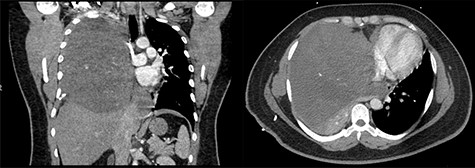

A 29-year-old male with history of Kawasaki’s disease presented with 1 week of cough, dyspnea on exertion, weight loss and fevers. His workup revealed a WBC of 13 K/μl (ref. 3.7–11.1 K/μl) and a 17 × 16 × 17.3 cm heterogenous mass with calcifications in the right hemithorax causing compression of the right lung and bronchus and left-sided mediastinal shift (Fig. 1). An echocardiogram demonstrated compression of the right heart from his mediastinal mass with a normal ejection fraction.

(Left to right) Coronal and axial images of 17 × 16 × 17.3 cm heterogeneous anterior mediastinal mass with compression of the right lung and left-sided mediastinal shift.